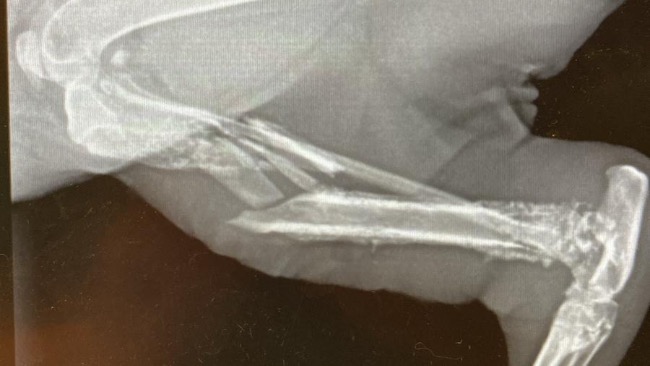

W lecznicy wykonano badanie krwi (morfologię i biochemię), badanie ortopedyczne, RTG, USG.

- kości kończyny z wielokrotnymi złamaniami,

- złamanie otwarte w przykurczonej kończynie,